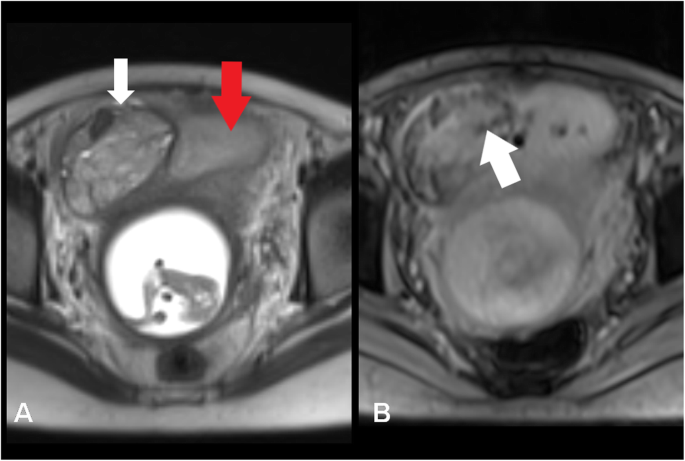

Unico Hospitals recently undertook a highly challenging MRI case of a 34-week pregnant woman to assess placenta previa and placental invasion with bladder. Such investigations are rarely performed in most centers due to the complexity of scanning at this advanced stage of pregnancy. The primary challenges included the patient’s inability to lie comfortably for a prolonged period and continuous fetal movement, both of which can significantly compromise imaging quality.

• To evaluate depth and extent of placental invasion (accreta, increta, per Creta).

• To assess possible bladder wall involvement.

• To differentiate between normal placenta and abnormally invasive placenta.

• To provide a road map for obstetric surgeons for delivery planning and potential surgical intervention.